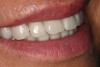

Upon delivery, the prosthesis was screwed into the implants and torqued to 15 Ncm. The screw access hole was filled with a plugging material to within 1 mm of the top of the sleeve. Composite material was then used to bring the screw access hole level with the surface acrylic. The procedure was repeated for the lower denture (Figure 10 and Figure 11).

Figure 10  Postoperative images of the patient’s restorative smile.

Figure 10

Figure 11  Postoperative images of the patient’s restorative smile.

Figure 11